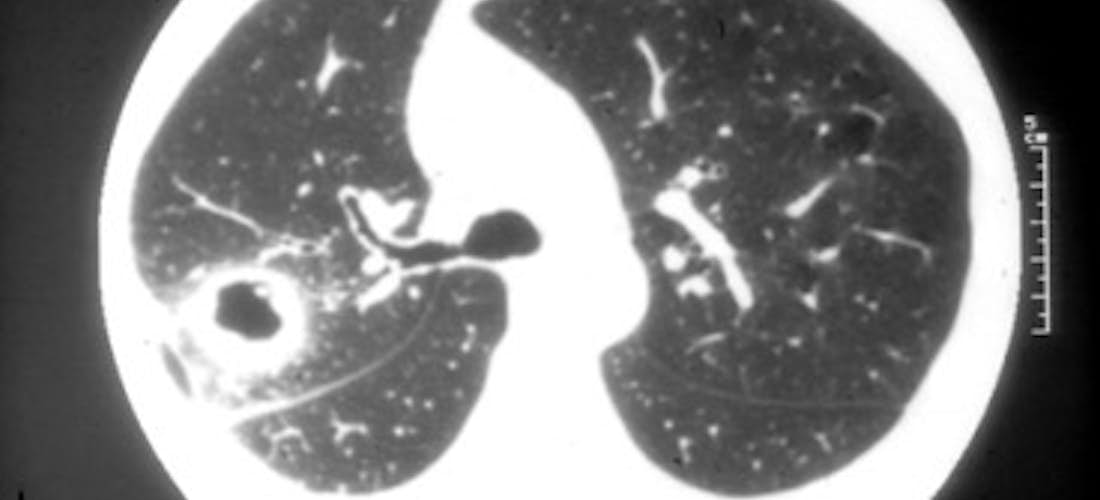

Les signes d'appel pulmonaires sont non spécifiques : toux, dyspnée, douleurs thoraciques, hémoptysie. La radiographie du thorax et le scanner montrent des nodules, unis ou bilatéraux, uniques ou multiples, excavés dans la moitié des cas (Clichés 3 et 4). Ils ont souvent une paroi épaisse. Ils peuvent être très nombreux mais, en général, inférieurs à 10. Leur survenue est parallèle à la progression de la maladie. Des infiltrats pulmonaires uni ou bilatéraux, peuvent également être observés. Un épanchement pleural s'y associe rarement. La fibroscopie bronchique peut mettre en évidence des sténoses (Cliché 5), conséquence de la granulomatose. Elles sont souvent très difficiles à traiter. On peut également mettre en évidence des masses pulmonaires granulomateuses pseudo-tumorales.